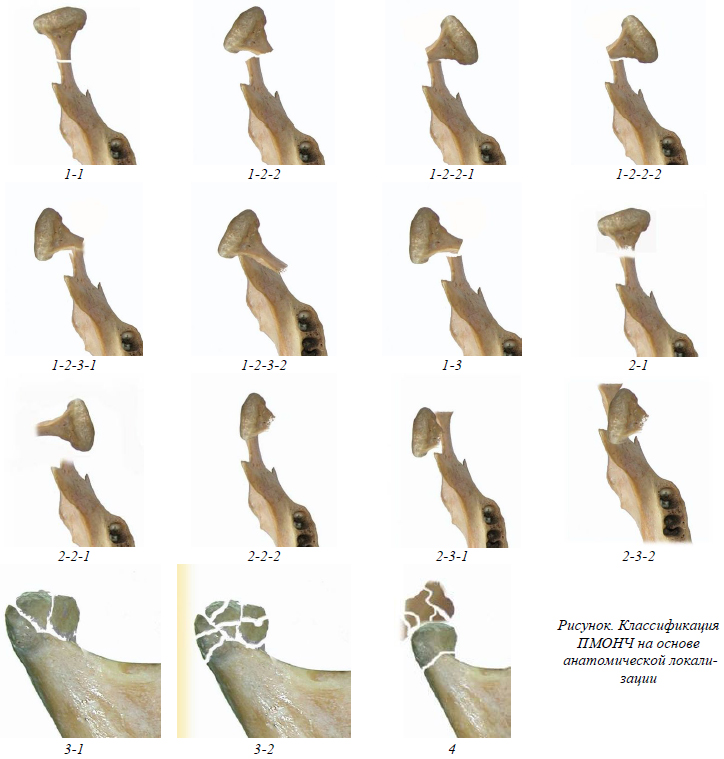

Непосредственно ПМОНЧ классифицируются нами на основе анатомической локализации с учетом описанных выше признаков (см.рис.).

Уровень – основание МОНЧ

- без смещения отломков

со смещением отломков

- с ротацией малого отломка вокруг оси МОНЧ

кнаружи

- с сохранением контакта между поверхностями излома

- без сохранения контакта, с захождением фрагментов и укорочением ветви НЧ

кнутри

- с сохранением контакта между поверхностями излома

- без сохранения контакта с захождением фрагментов и укорочением ветви НЧ

- с вывихом в ВНЧС

Уровень – шейка МОНЧ (с возможным повреждением элементов ВНЧС)

- без смещения отломков

со смещением

- кнаружи

- кнутри

с вывихом в ВНЧС

- кнаружи

- кнутри

- кпереди

- кзади

Уровень – головка МОНЧ (с повреждением элементов ВНЧС)

- крупнооскольчатый

- мелкооскольчатый

- С повреждением элементов суставной ямки и внедрением головки МОНЧ в среднюю черепную ямку.